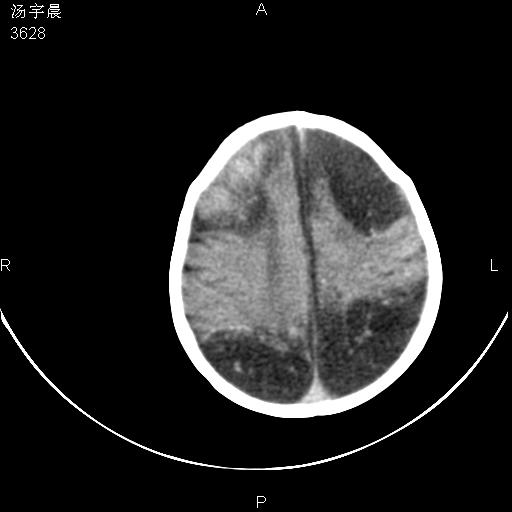

早产儿,现两月大,2月份在某医院诊断病毒性脑炎并治疗,mri报右颞部脑白质片状长t2信号,脑白质模糊。其他不详,现家属要求ct复查 。

双侧大脑半球大片状低密度,无明显占位表现, 符合病毒性脑炎。

小儿病毒性脑炎ct表现缺乏特异性,但其定位分布有一定特异性,单纯疱疹病毒性脑炎ct表现以颢叶病变为主,同时可累及其他脑区或伴出血,乙型脑炎表现为基底及丘脑的病变,流行性腮腺病毒性脑炎则ct表现可正常,故ct检查对病毒性脑炎的定性有重要的价值。 本例支持:病毒性脑炎的后遗改变!